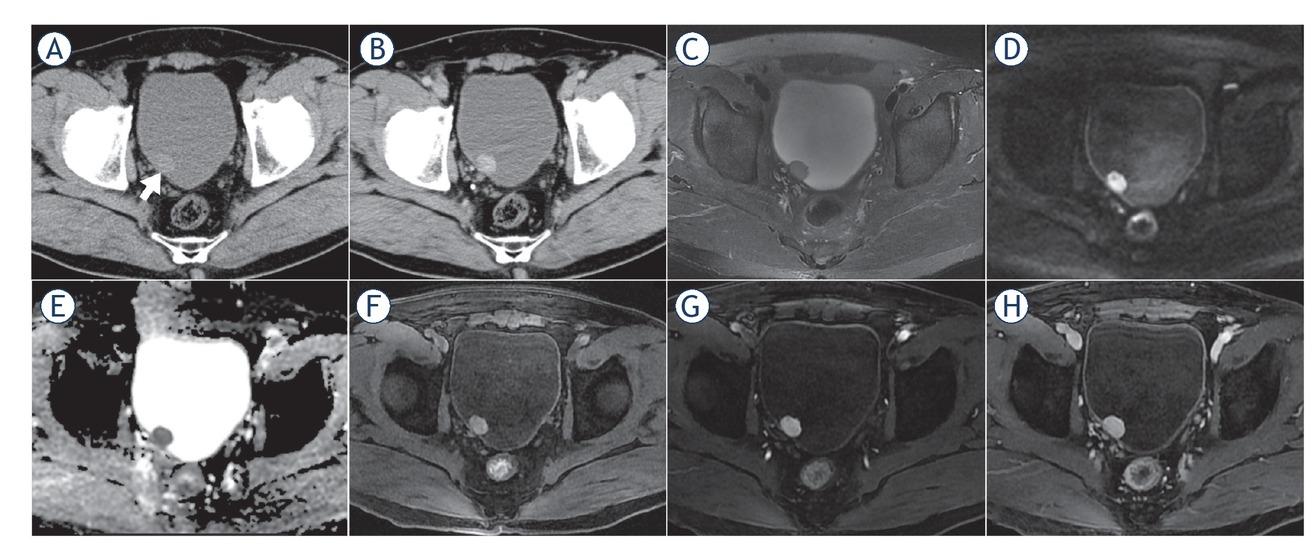

CT and MR images of a 61-year-old male patient with bladder paraganglioma. The tumour was located in the posterior bladder wall, oval, well-defined margin, protruding into the bladder cavity with broad-base attachment to the bladder wall (short arrow). The lesion showed slight hypodensity and obvious enhancement on axial pre- and post-contrast-enhanced CT images (A, B), homogenous slight hyperintensity on T2-weighted images (T2WI) (C), marked hyperintensity on diffusion-weighted images (DWI) (D), hypointensity on apparent diffusion coefficient (ADC) maps (mean ADC value, 0.870 × 10-3 mm2/s) (E), hyperintensity compared to the gluteus maximus on T1-weighted images (T1WI) (F) and “fast in and slow out” on dynamic contrast-enhanced MRI (G, H).

On non-contrast CT images, the lesions mainly demonstrated homogeneous and soft-tissue density, with CT values ranging from 19.9 to 55.2 Hounsfield Units (HU). Intra-tumoural cystic degeneration or necrosis was rare (2/16). All lesions showed moderate to marked enhancement in the arterial phase of contrast-enhanced CT images (Table 3), with CT values of 64.3–117.9 HU, which were about 2.3 times that of the CT value on pre-contrast enhanced images (Figure 4A–B). In the two patients with multiple paragangliomas, the density and enhancement pattern of lesions in the non-bladder sites were similar to those in the bladder.

On T2WI, the lesions demonstrated homogenous hyperintensity (10/16), higher than the gluteus maximus and lower than the urine in the bladder, without typical “pepper and salt” sign. Due to the restricted diffusion, the lesions showed hyperintensity on DWI and hypointensity on ADC maps (mean ADC value ± standard deviation, 0.883 ± 0.126×10-3 mm2/s). On T1WI, the lesions showed hyperintensity and averaged 1.4 times higher than that of the gluteus maximus at the same layer. Following MRI enhancement, the BPGs all had obvious enhancement in the arterial phase (an average of 2.5 times higher than the tumour signal intensity on T1WI), slightly decreased enhancement in the venous phase and the delayed phase (an average of 2.4 and 2.0 times higher than the tumour signal intensity on T1WI, respectively), exhibiting a “fast in and slow out” enhanced pattern (Table 3, Figure 4C–D). Similar to CT findings, the two patients with multiple paragangliomas showed comparable MRI findings between the bladder and non-bladder lesions.

Imaging methods are primarily used for localization of the paraganglioma.11 In the absence of typical clinical manifestations and negative biochemical tests, imaging can also be used as a complementary approach for qualitative diagnosis. CT has a high sensitivity (82%) in detecting extraadrenal pheochromocytoma.9 We demonstrated that most BPGs are typically present as a solitary lesion protruding into or out of the bladder cavity, with an oval shape, soft tissue density, well-defined margin and a broad-base attachment to the bladder wall. The tumour exhibits slightly lower density and early marked enhancement on the contrast-enhanced CT images. Contrary to the previous literature, T2WI showed that BPGs are mostly homogeneous and high-intensity, without the typical “pepper and salt” appearance.12,13 The homogenous nature may be due to the fact that the lesion was still small when it was detected, and intratumoural degeneration has not yet occurred. Similar to bladder cancer, BPGs show marked hyperintensity on DWI and hypointensity on ADC maps due to restricted diffusion of water molecules.14 The tumours presented slight hyperintensity on T1WI and “fast in and slow out” enhanced pattern on contrast-enhanced images, which may be distinctive MRI features of BPGs.10,15 The potential pathological bases for the above imaging findings are that the tumour cells are large with abundant cytoplasm and the intercellular stromata are rich in blood vessels showing fissure or haemangiomalike dilatation.16